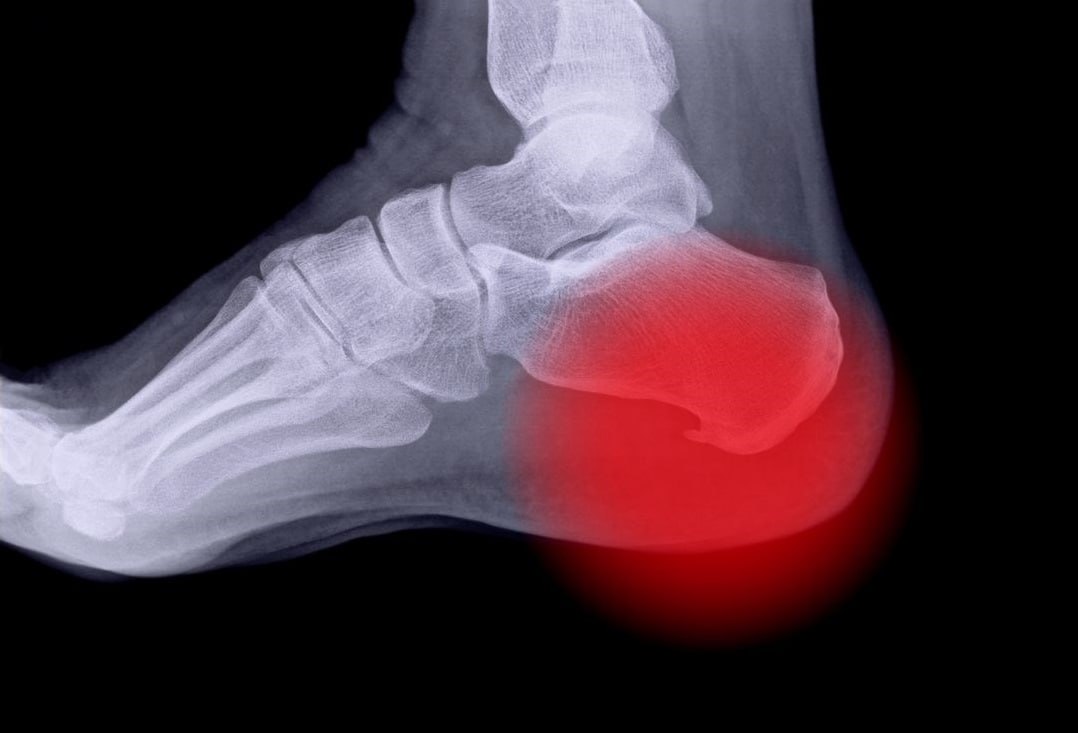

Пяточная шпора — это неофициальное, но широко распространённое название плантарного фасциита. Речь идет о воспалении соединительной ткани (фасции), проходящей от пятки к пальцам стопы. В месте прикрепления фасции к пяточной кости может образоваться костный нарост, который и называют "шпорой".

• Острая боль в пятке, особенно при первых шагах утром

• Боль локализуется ближе к внутреннему краю пятки

Важно: интенсивность боли не всегда зависит от размера шпоры. Даже небольшой нарост может вызывать сильный дискомфорт.